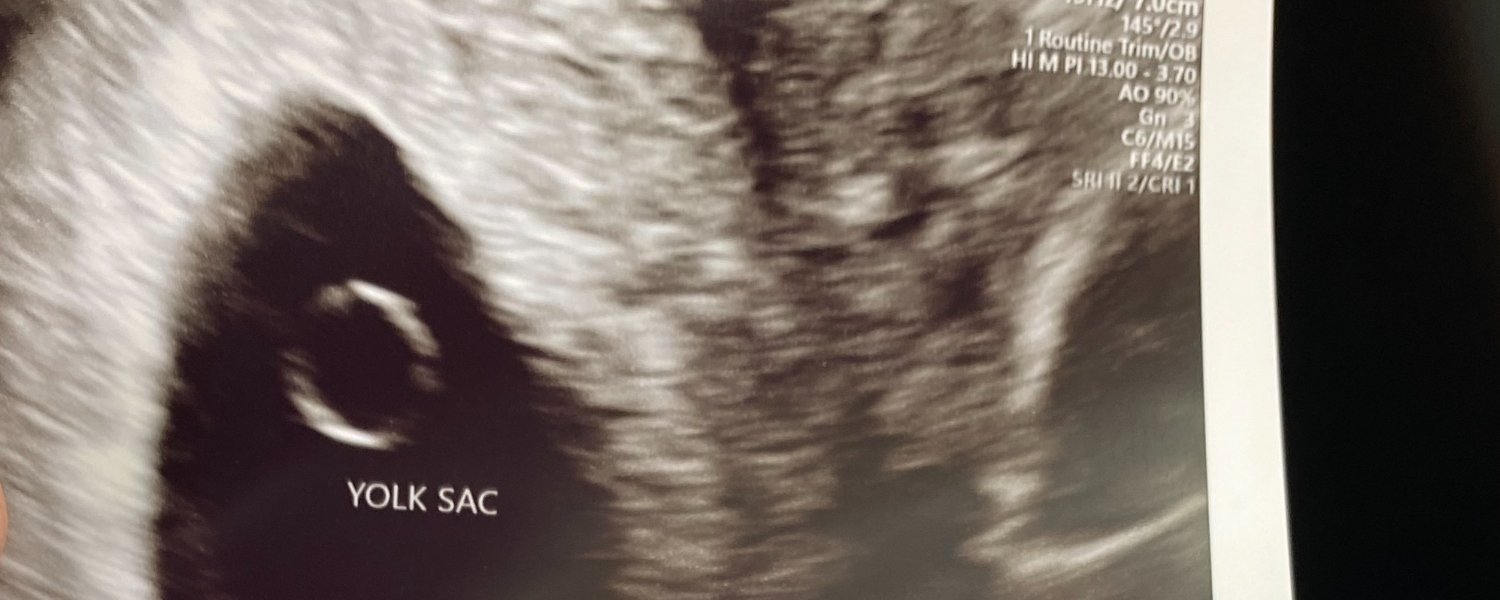

We didn't expect to get pregnant again so quickly. We had even been discussing closing the door on growing our family after our third loss. But our desire for raising a third child was impossible to shake. And we desperately wanted a happy ending to this chapter of our lives. We were afraid of what others would think when we got pregnant again. "Why are they doing this to themselves?" "Can't they be happy with the kids they have?" "Isn't enough enough?" "Can't they take 'no' for an answer?" We considered all of these questions, too... And many of them kept me up at night when I started to feel early symptoms of this pregnancy. We told only a select few people so they could share in our joys and fears together, but waited to tell most of our friends and family after our first ultrasound. We decided not to get blood work and to wait until I was 8 weeks to go in for an ultrasound. To our utter surprise, there she was, a beautiful baby with a strong heartbeat. Honestly, we expected silence. We had grown so familiar with and even expectant of bad news. This was the absolute best kind of shock, and we rode the wave of pleasant disbelief all day long. We took home our ultrasound photos that marked "BABY!" in a little envelope that said "Baby on the way" in our nurse's handwriting. We sat through an (honestly, painful) appointment with the nurse navigator who walked us through what to expect at the delivery and resources for pediatricians and lactation consultants. (Yes, they did all of this at our 8 week appt. with a parents who had 3 losses under their belts). We wanted out of there, but were trying to savor the little waves of hope that these things could really apply to us in just 7 months. We decided to tell our family at Christmas, because after all, my other early losses never came with a heartbeat at that first appointment. So while a later loss was definitely still possible – and we knew it all too well – this milestone was a good sign. Just over a week later at 9 weeks, after just telling all of our family about our new baby on the way, I went in for a transfer appointment at a new OBGYN. The midwife offered an ultrasound (which wasn't scheduled) and I jumped at the opportunity to see the baby again. There was no tech there that day, so she offered to do it herself. She couldn't quite see what she wanted to see via an abdominal ultrasound, so she scheduled one at another location with a tech where Theo came to meet me. Theo had a pit in his stomach, but I was not concerned. I had this peace – overflowing really – like I was sure the baby was fine. But my intuition was wrong... One week after I had seen a beautiful, strong heartbeat, we met stillness again. Ivy Rose – a girl with Turner Syndrome, we learned from a 3rd D/C in January 2024. This baby was the first to give us a reason for her passing. Some babies with this diagnosis go on to have a normal pregnancy and live a pretty normal life. But most die in utero – many in the later trimesters. As devastated as we were to lose her now, we felt spared from another late-term loss.